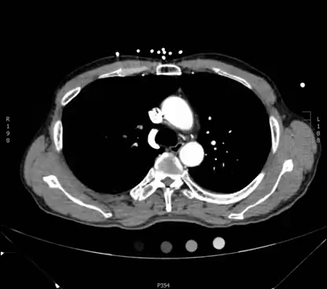

Here is an example CT scan in the axial plane:

Here is another example CT scan in the axial plane: